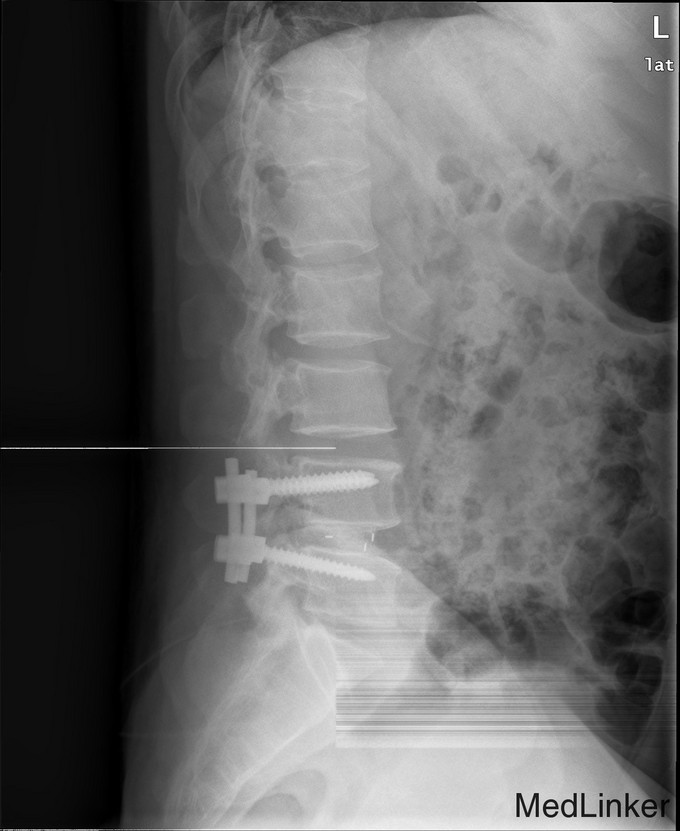

游离型腰椎间盘突出症的手术治疗

腰痛伴右下肢疼痛一周

查体 辅查

腰椎前屈受限,腰34,45右侧棘突旁压痛,放射痛(+),右下肢直腿抬高试验阳性,右小腿皮肤感觉减退

诊断 处理

腰椎间盘突出(游离型) 腰后路减压+髓核摘除椎间融合+植骨内固定